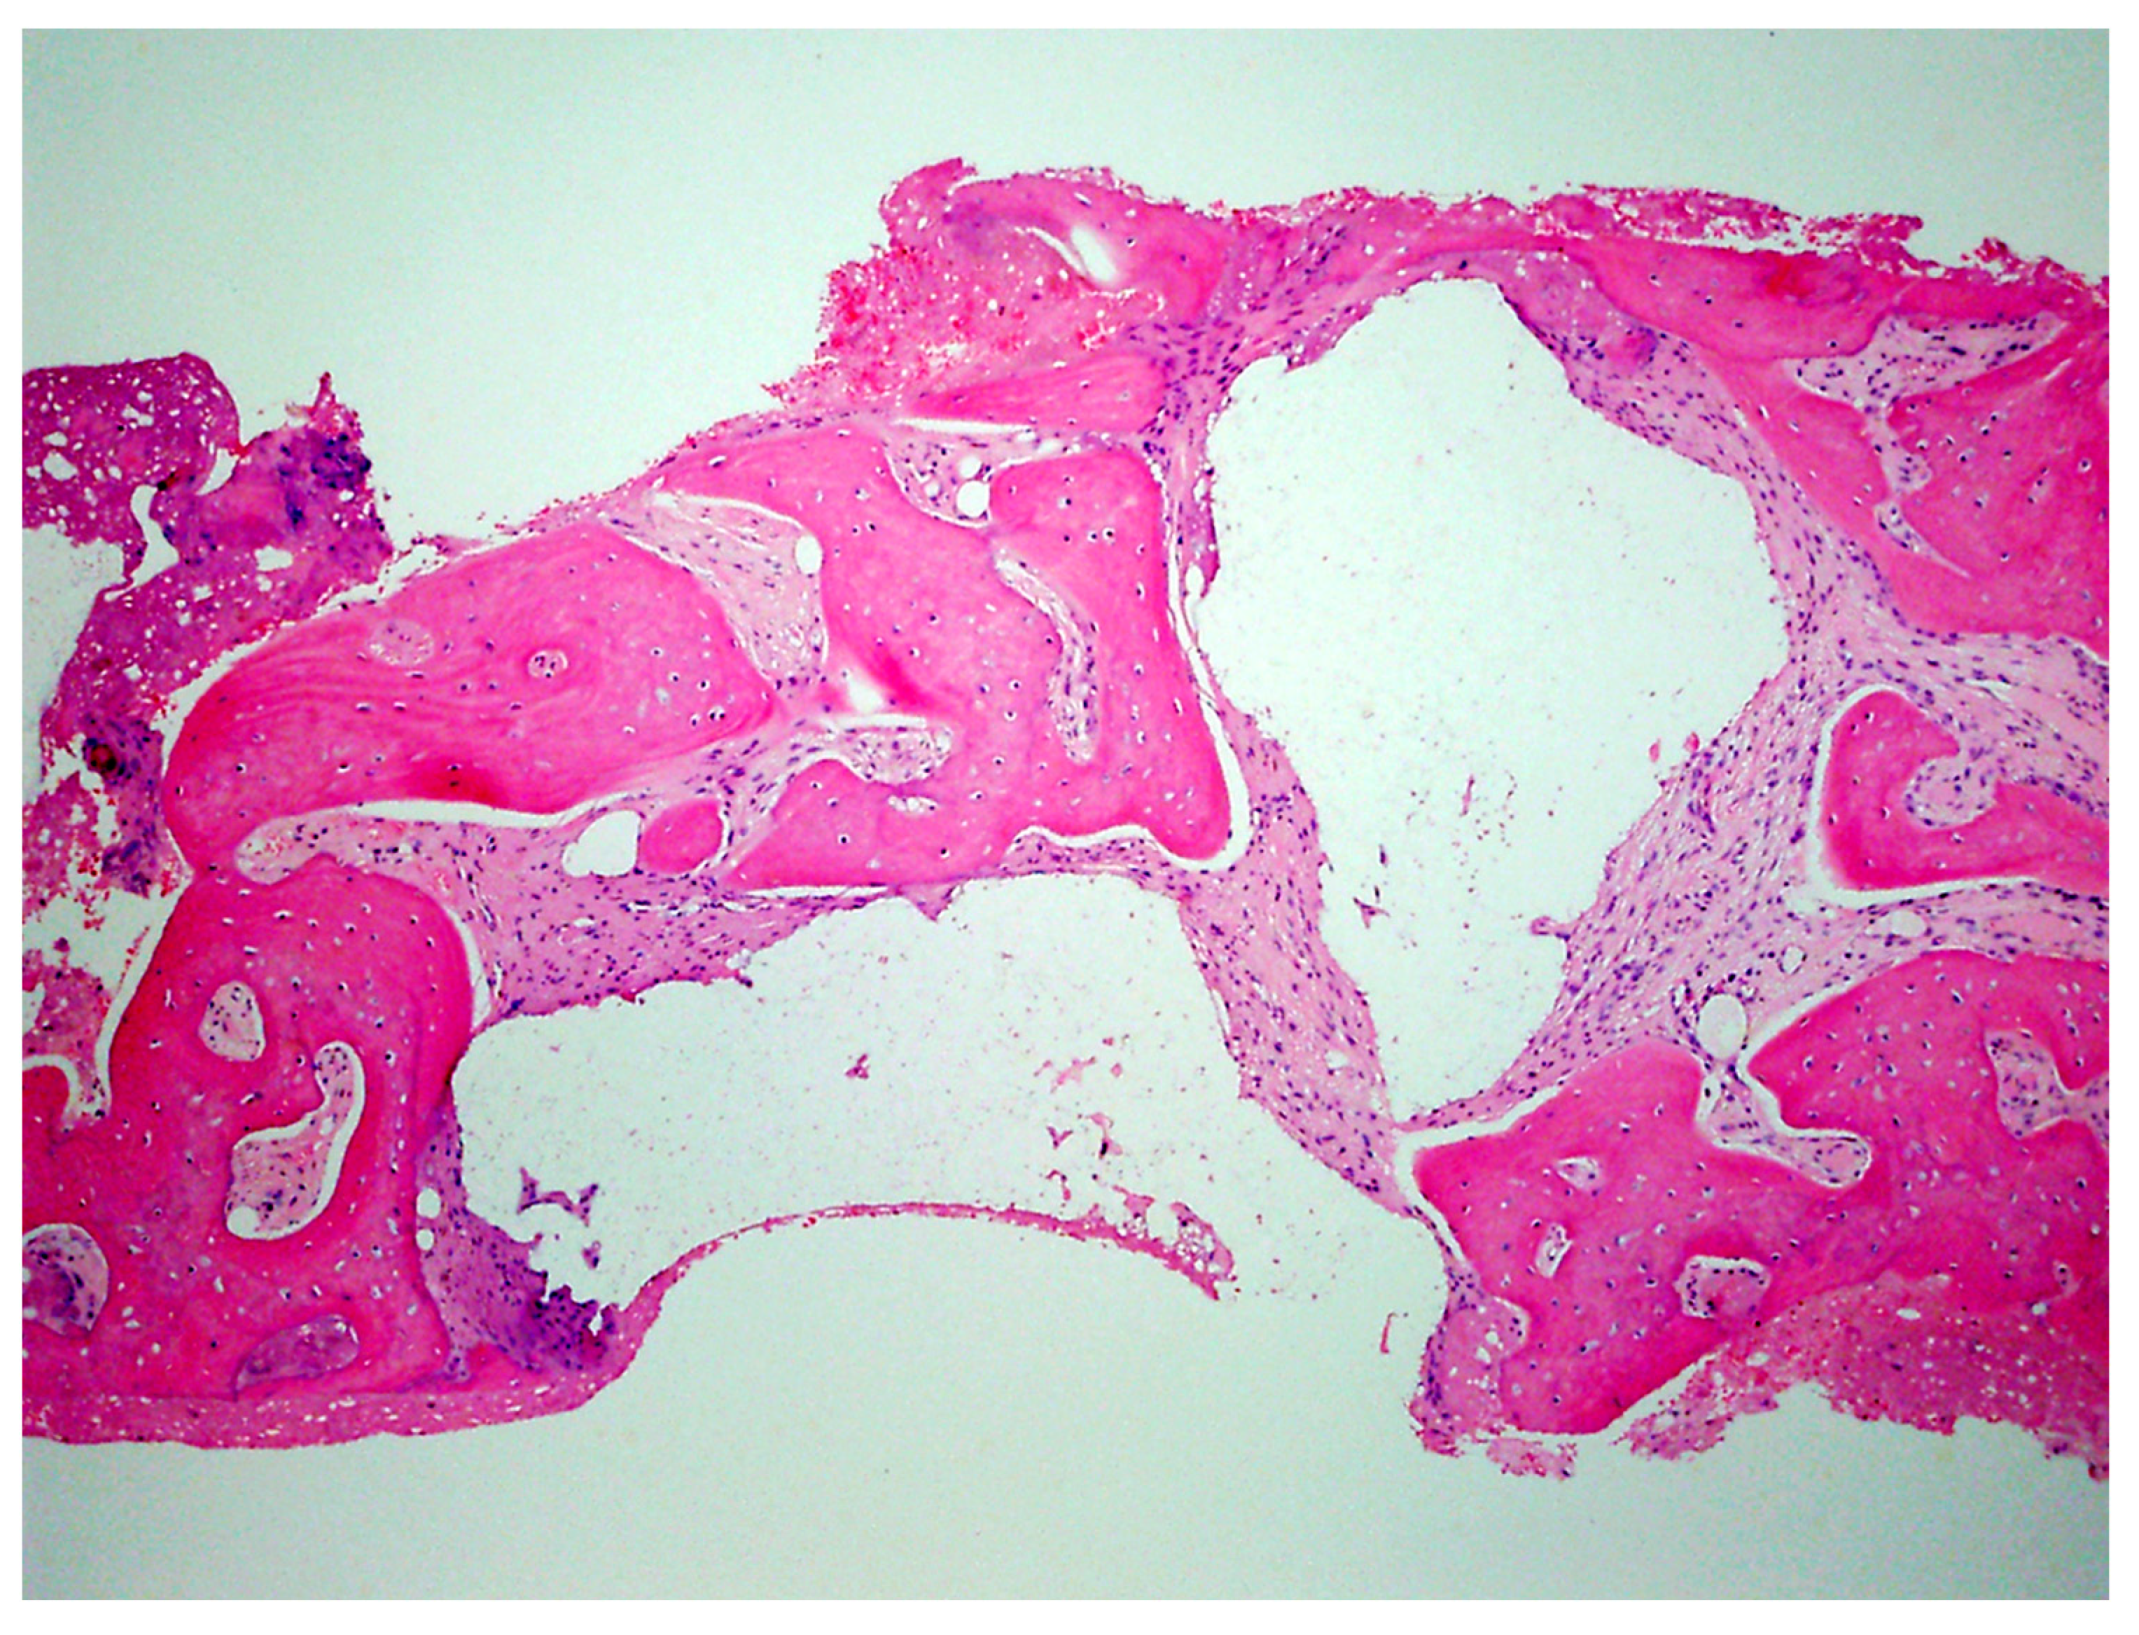

A critical question is about what happens histologically to the graft and at what stage during healing. For example, when delayed socket grafting was performed at a site where a large defect was present following extraction (Figure 18, left), a healing period of 3 weeks post-extraction was needed, allowing primary closure post-graft. This gives us more predictability and simpler surgery, plus two attempts to clean the site. EthOss graft material was placed into the socket (Figure 18, middle) and primary closure with the flap was achieved and secured with sutures (Figure 18, right). Intraoral physical exam and radiographic measurement showed all sites to have regenerated vertically 3–6 mm and horizontally 4–6 mm with new host bone allowing for successful placement of the implants. A core sample was obtained from one case to confirm the series to be in line with earlier findings. Histology was performed by core biopsy at 10 weeks following graft placement and demonstrated well-preserved reactive (woven) trabecular bone with intertrabecular tissue composed of uniformly collagen-rich myofibroblastic tissue and 60% of the core consisting of bone (Figure 19).

Figure 19.

Histology of the core sample obtained following 10 weeks of graft site healing demonstrating well preserved reactive (woven) trabecular bone with intertrabecular tissue composed of uniformly collagen-rich myofibroblastic tissue and 60% of the core consisting of bone.